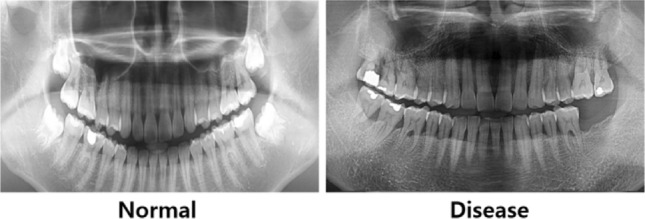

Tufts dental database (TDD)32 is a collection of one thousand digital panoramic radiographs that have not been completely supervised. The data was collected with the agreement of the Tufts University Institutional Research Board (IRB ID MODCR-01-12631, authorized on 7/14/2017). The images during the period spanning from January 1, 2014, to December 31, 2016 were carefully selected based on their diagnostic accuracies, along with a focus of minimizing technical faults. The radiographs were converted to a standard picture format (TIFF/JPEG) and were annotated by both a dental specialist and a student using the Labelbox program. The annotations specifically targeted dental masks and maxillomandibular RoIs, which were used as the reference data for training UNet model that learns to recognize important structural components for automated detection of periodontal disorders. Figure 4 presents sample panoramic radiographs of normal (left panel) and periodontal disease (right panel) in the TDD.

Fig. 4.

Sample panoramic radiographs from tufts dental database.